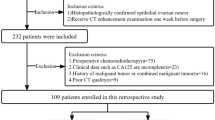

We performed a retrospective analysis of patients with epithelial ovarian cancer who received treatment at our institution from March 2017 to July 2020. We collected clinical pathological data, CT enhanced images before surgery, radiotherapy, and chemotherapy, and postoperative pathological diagnosis. The inclusion criteria were as follows: (1) epithelial ovarian cancer pathologically confirmed by biopsy; (2) abdominal CT scan performed before the operation, and the images including the arterial, venous, and delayed phases; (3) no radiotherapy or chemotherapy performed before the operation; (4) lesion size ≥ 10 mm. The exclusion criteria were as follows: (1) large image artifacts interfering with observation; (2) intolerance to enhanced CT examination; (3) preoperative radiotherapy and chemotherapy; (4) a history of other malignant tumors or pelvic metastases. In total, 106 patients were included in the study (Fig. 1). Among them, 63 cases, aged 35–75 years (average: 54.86 years), were in the BRCA gene non-mutation group; 43 cases aged 36–77 years (average: 53.93 years), were in the BRCA gene mutation group.